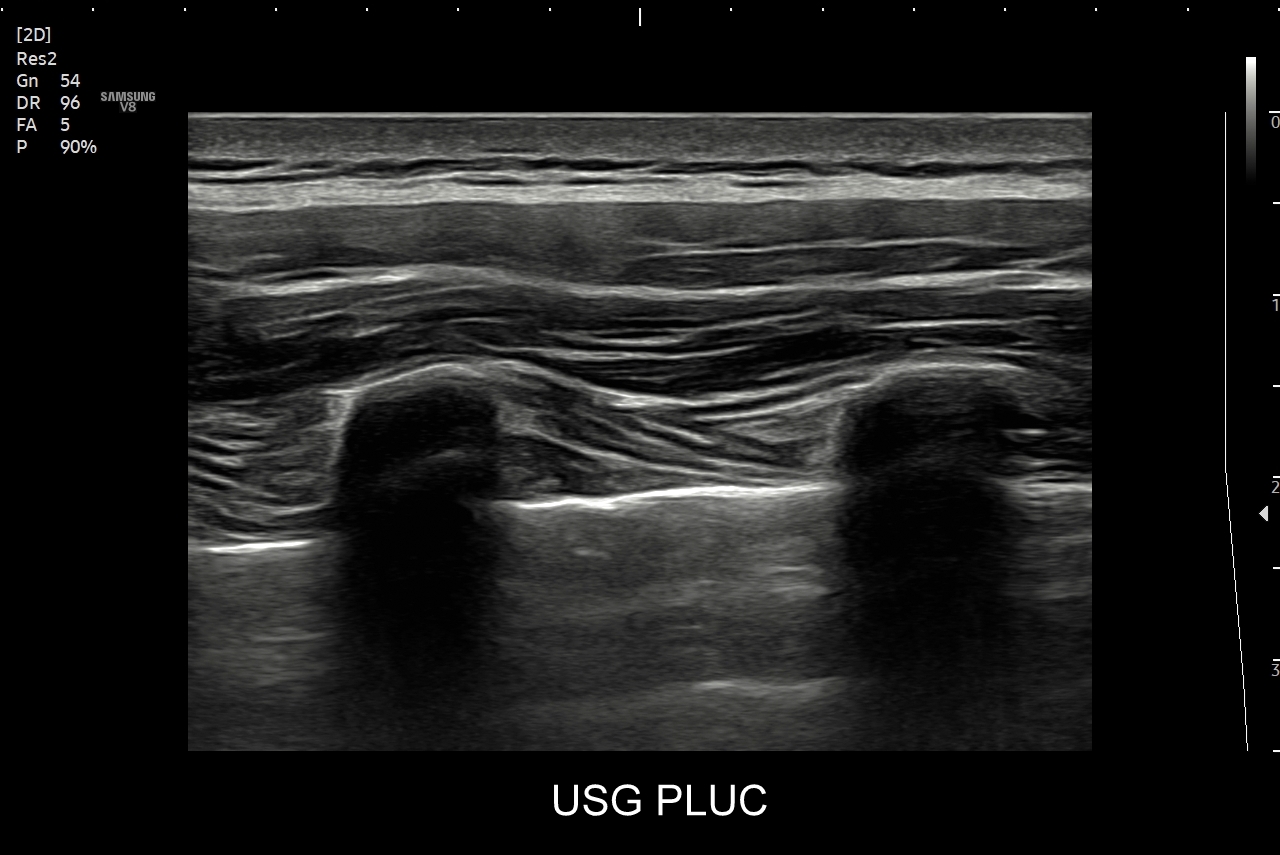

Ultrasonografia płuc oparta jest o fizykę fal akustycznych. Wychwytuje zarówno schorzenia lokalizujące się w zewnętrznych partiach płuc oraz w jamach opłucnowych w postaci realnego obrazu, ale także wykazuje istotne diagnostycznie informacje z głębszych partii narządu na podstawie specyficznych artefaktów generowanych przez patologie wewnątrz płuca.

Kluczem do wartościowego zastosowania metody USG w diagnostyce pulmonologicznej jest zrozumienie jej możliwości oraz ograniczeń. USG jest niezwykle czułym badaniem w diagnostyce zapaleń płuc zarówno płatowych, jak i atypowych, np. wywołanych przez Mycoplasma lub Chlamydia. W przypadku zapalenia płuc pojawienie się widocznych zmian sonograficznych wyprzedza wystąpienie fenomenów osłuchowych wykrywanych przy osłuchiwaniu klasycznym stetoskopem. Metoda USG jest również bardzo czuła w diagnostyce chorób opłucnej i jam opłucnowych, takich jak nowotwory opłucnej, odma odma opłucnowa czy płyn w jamie opłucnowej. W rękach doświadczonego lekarza badanie USG może być przydatne w wykryciu zatorowości płucnej, a nawet guzów nowotworowych płuc.